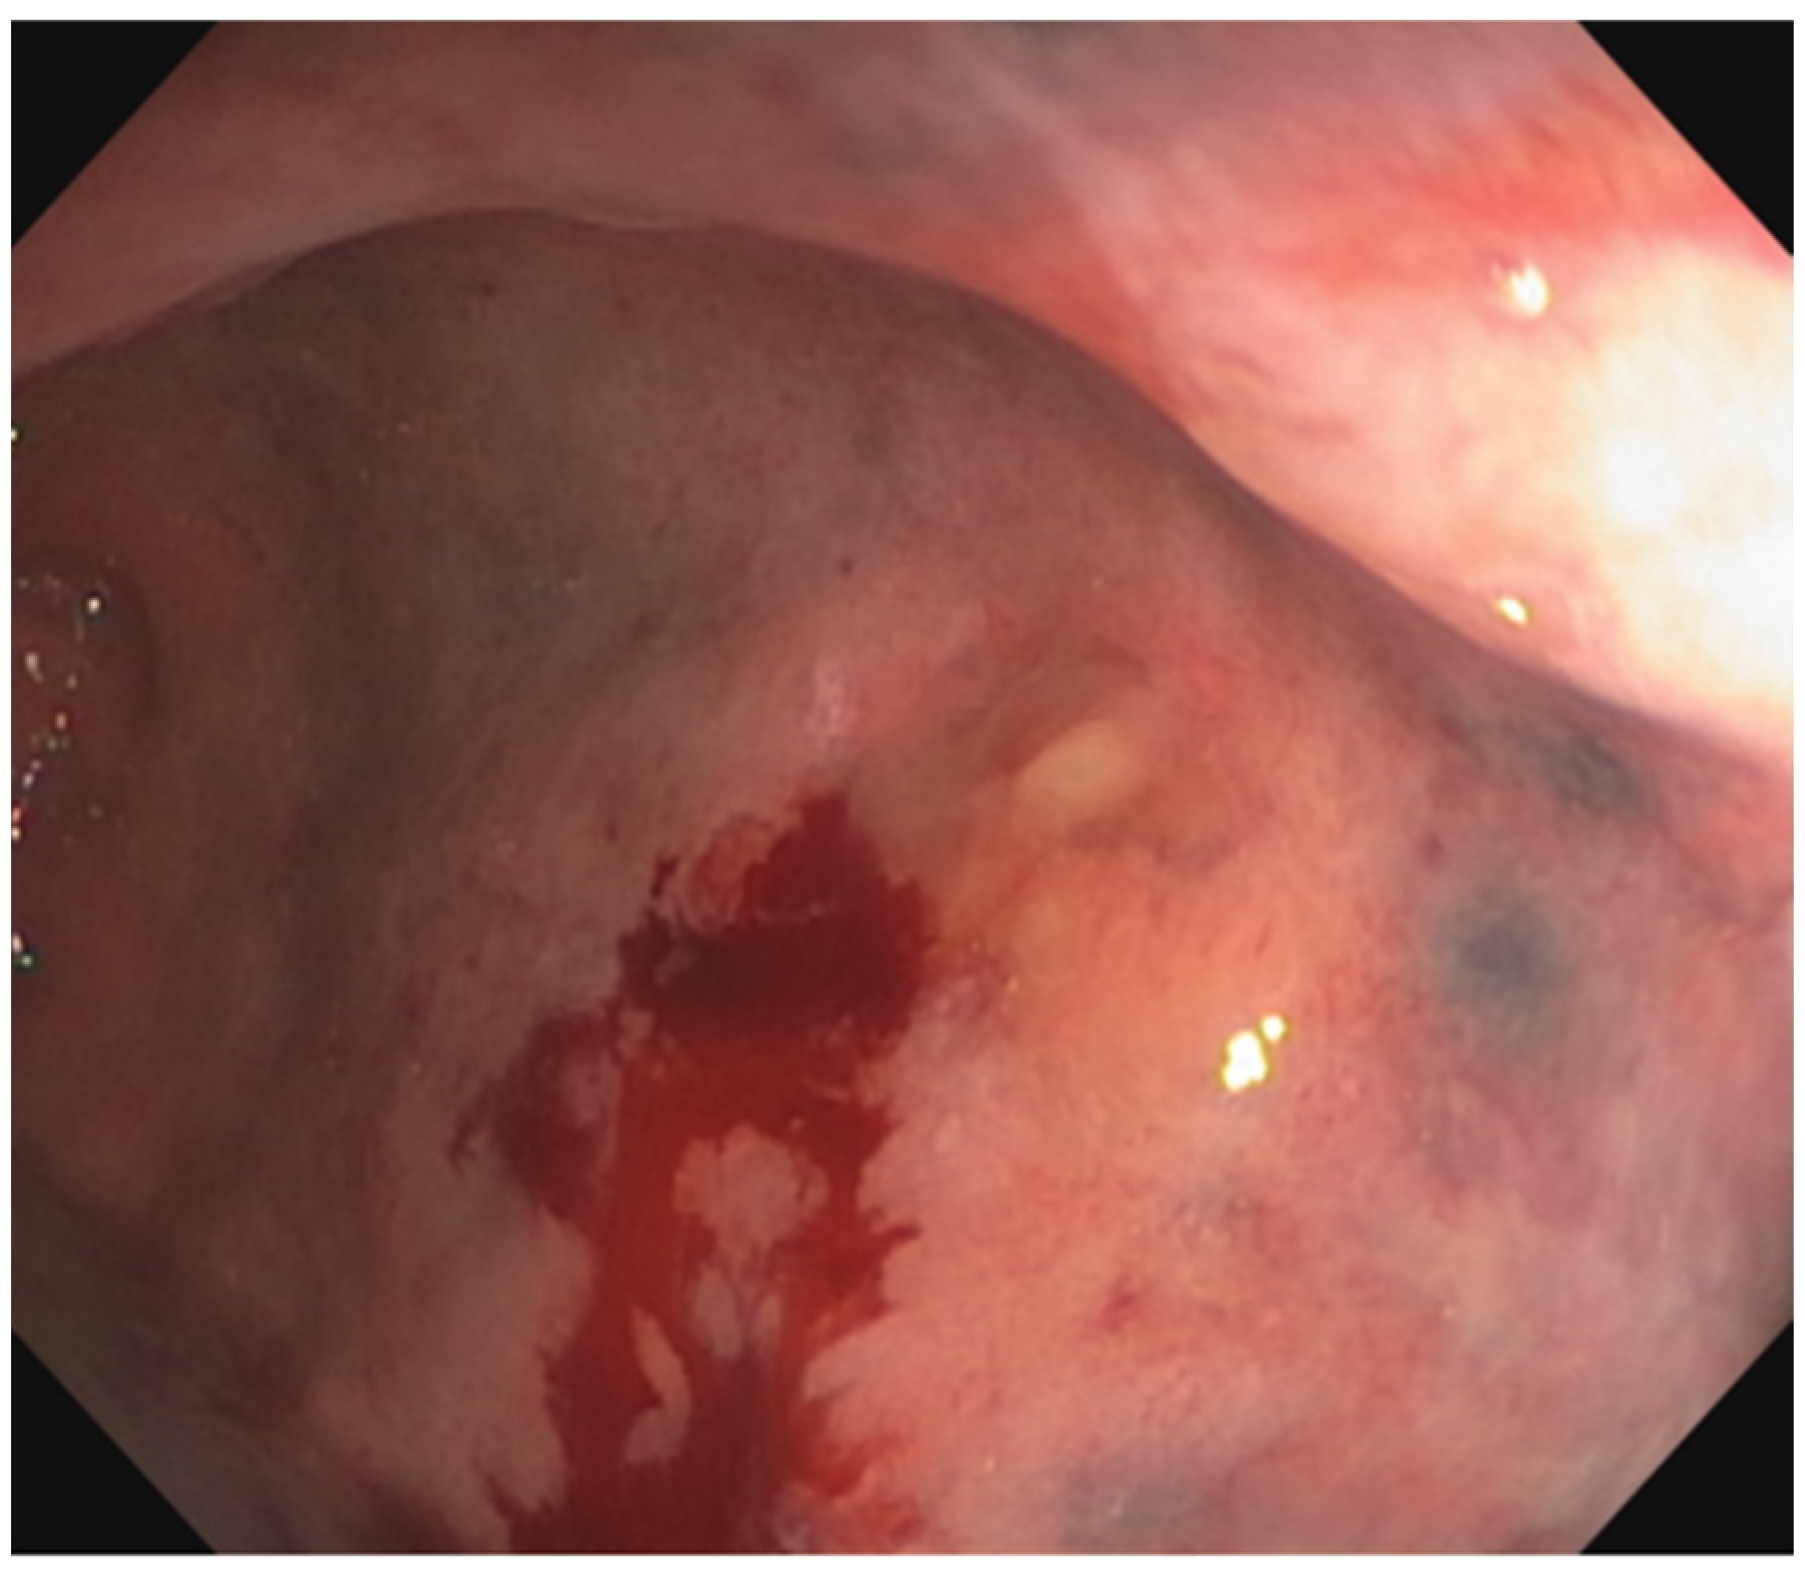

3. Direct Beam Radiation Damages Surrounding Organs

6. Assessment, Surveillance and Diagnosis

- Porouhan, P.; Farshchian, N.; Dayani, M. Management of radiation-induced proctitis. J. Fam. Med. Prim. Care 2019, 8, 2173–2178. [Google Scholar] [CrossRef]

- Goldner, G.; Tomicek, B.; Becker, G.; Geinitz, H.; Wachter, S.; Zimmermann, F.; Wachter-Gerstner, N.; Reibenwein, J.; Glocker, S.; Bamberg, M.; et al. Proctitis after external-beam radiotherapy for prostate cancer classified by Vienna Rectoscopy Score and correlated with EORTC/RTOG score for late rectal toxicity: Results of a prospective multicenter study of 166 patients. Int. J. Radiat. Oncol. Biol. Phys. 2007, 67, 78–83. [Google Scholar] [CrossRef]